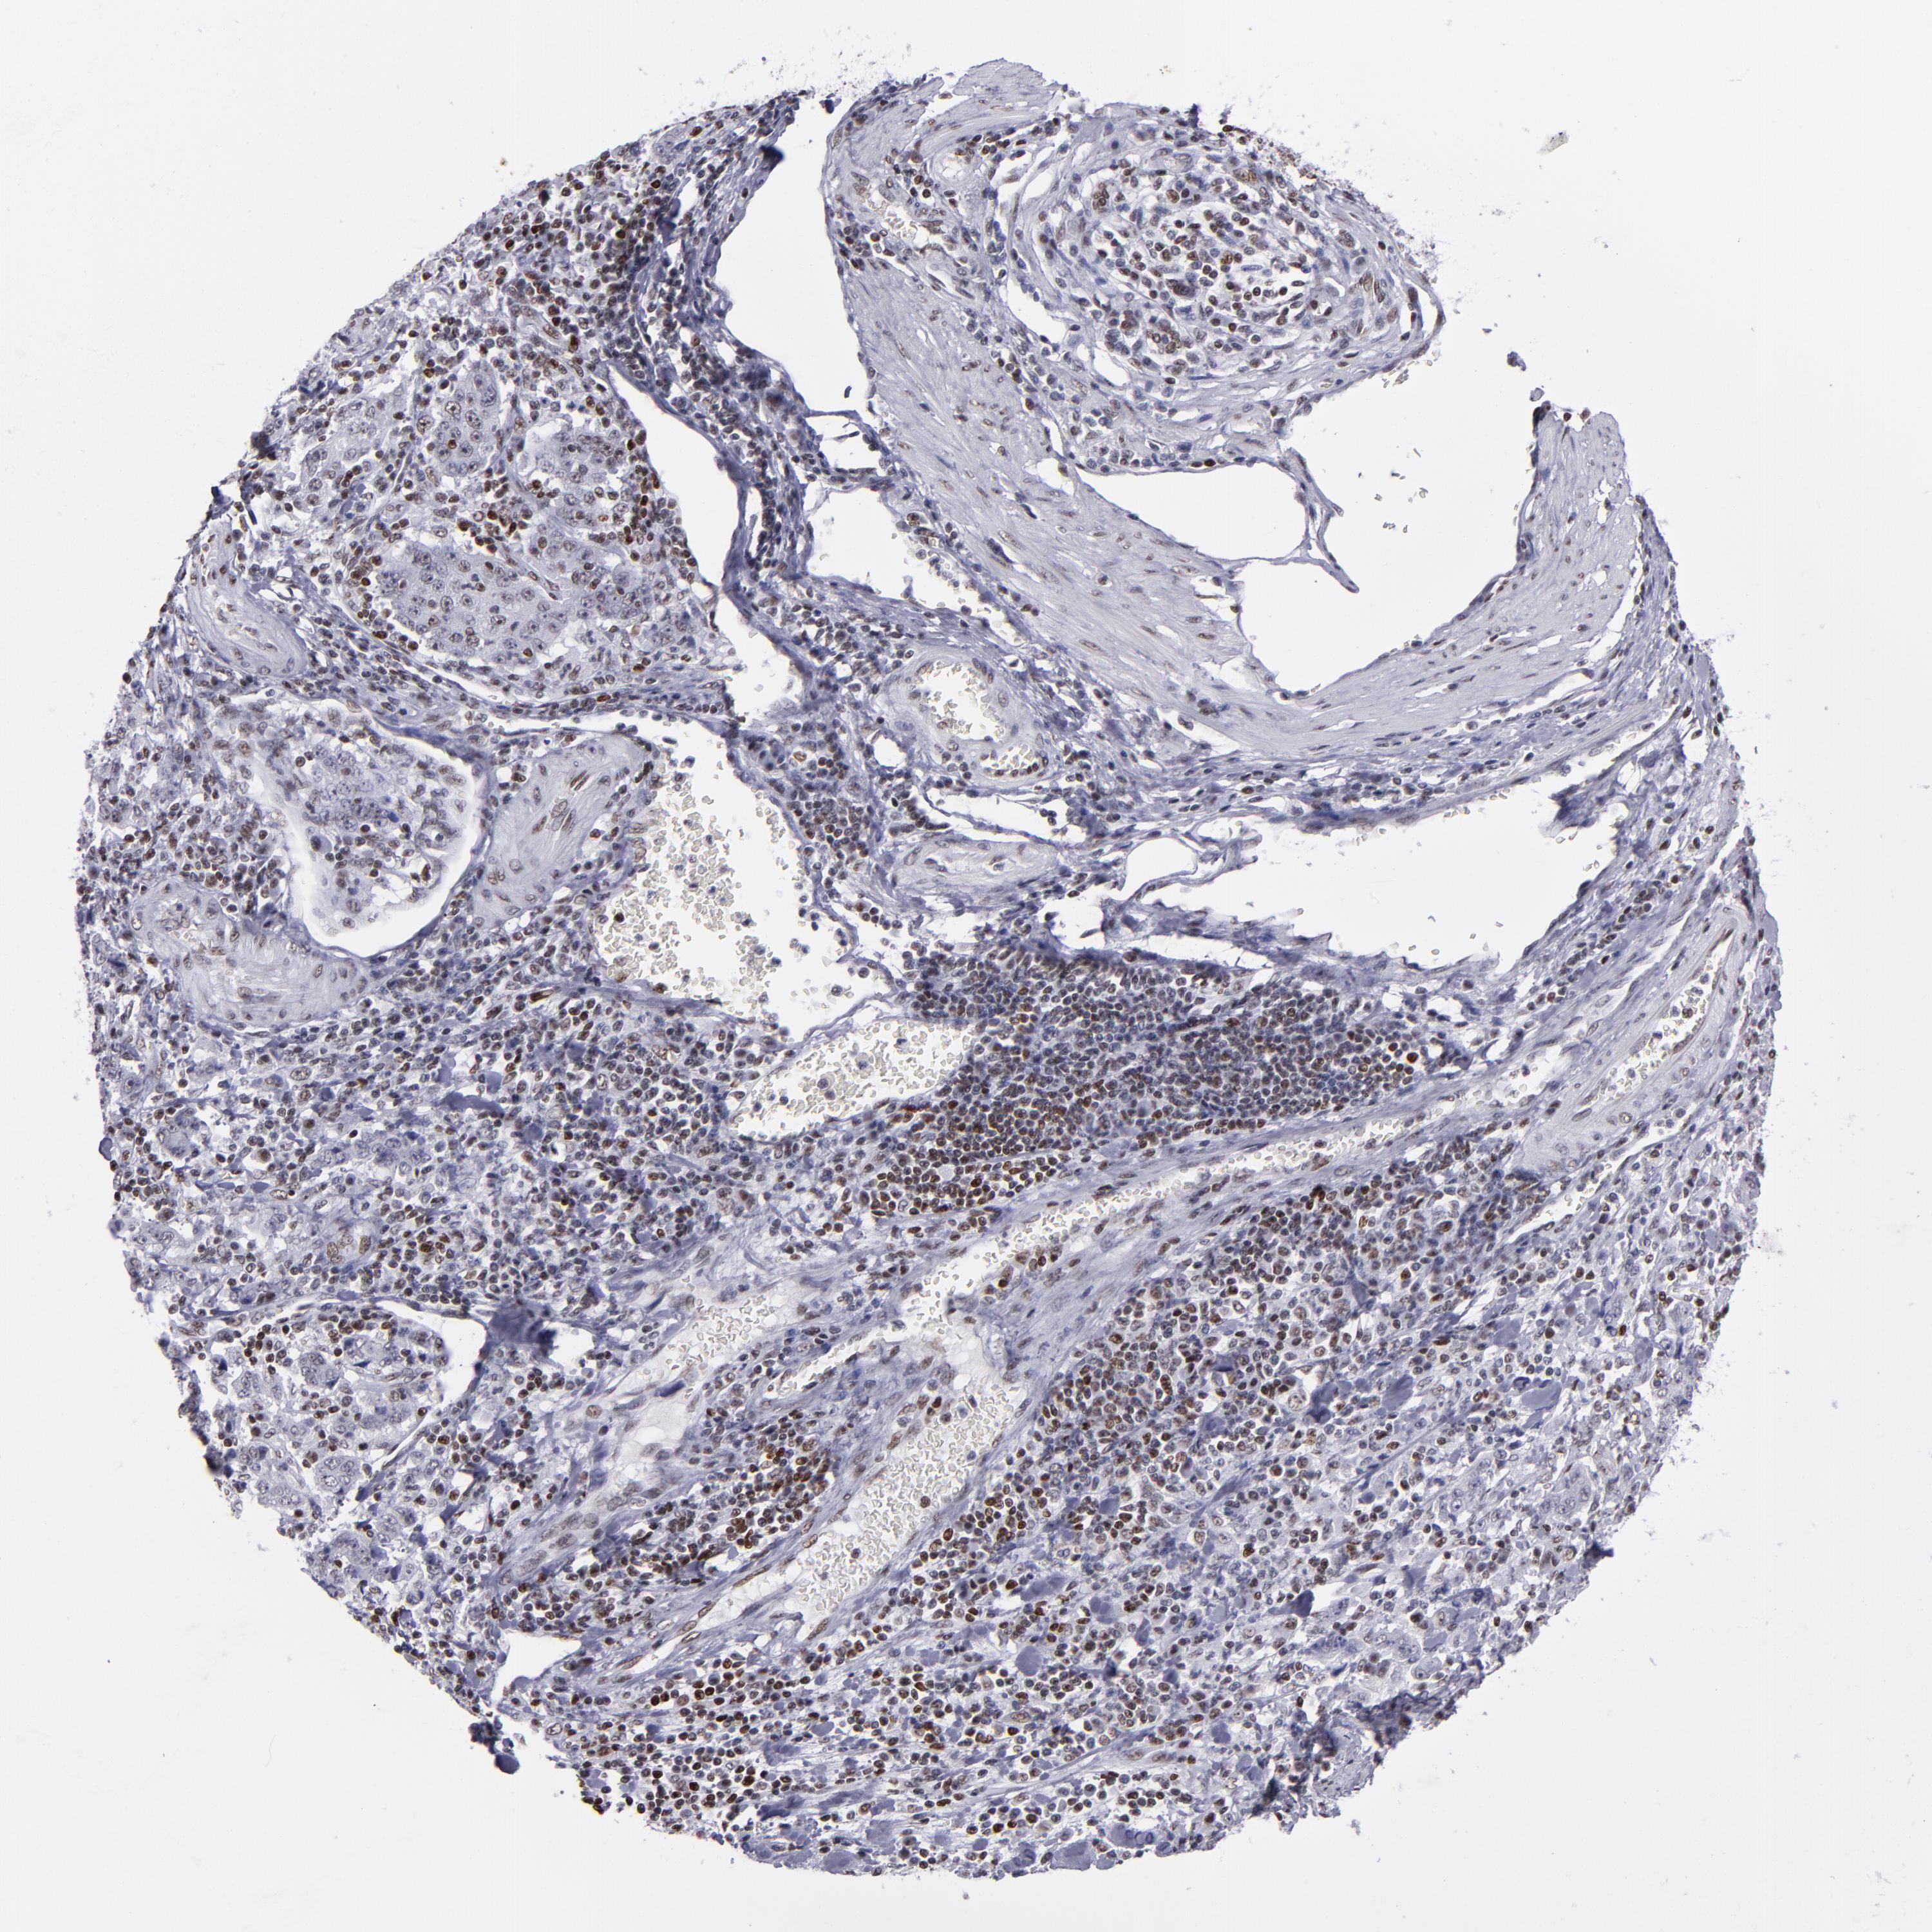

STOMACH CANCER - Protein expressioni

A mouse-over function shows sample information and annotation data. Click on an image to view it in a full screen mode. Samples can be filtered based on level of antibody staining by selecting one or several of the following categories: high, medium, low and not detected. The assay and annotation is described here.

Note that samples used for immunohistochemistry by the Human Protein Atlas do not correspond to samples in the TCGA dataset.

Antibody stainingi

Antibody staining in the annotated cell types in the current human tissue is reported as not detected, low, medium, or high, based on conventional immunohistochemistry profiling in selected tissues. This score is based on the combination of the staining intensity and fraction of stained cells.

Each image is clickable and will lead to virtual microscopy that enables deeper exploration of all samples and also displays staining intensity scores, fraction scores and subcellular localization as well as patient and tissue information for each sample.

Antibody HPA001907

Antibody HPA002735

Antibody CAB010451

Antibody CAB080271

Staining

High

Medium

Low

Not detected

Intensity

Strong

Moderate

Weak

Negative

Quantity

>75%

75%-25%

<25%

None

Location

Nuclear

Cytoplasmic/membranous

Cytoplasmic/membranous,nuclear

Adenocarcinoma, NOS

Adenocarcinoma, High grade